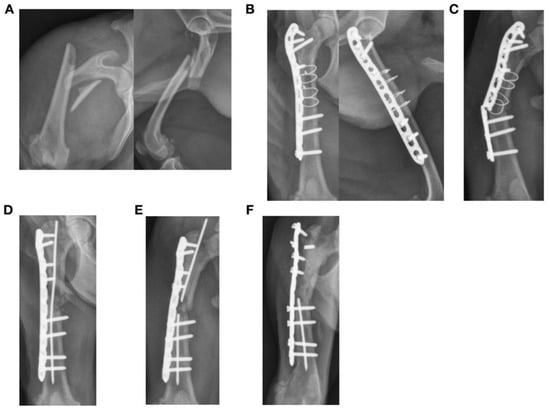

3.3. Plate Failure (11 Fractures)

| 1 | Y | Tibia | Diaphyseal | Y | N | 12 | 10 | 12 | 0.83 | 71.9 | 3.5 | 38.5 | 3.5 mm DCP | 32.94 | Medial |

| 2 | Y | Tibia | Diaphyseal | Y | Y | 13 | 7 | 8 | 0.62 | 95.8 | 2.6 | 41.4 | 1.5/2.0 LCP | 0.79 | Medial |

| 3 | N | Tibia | Diaphyseal | Y | N | 11 | 9 | 10 | 0.91 | 77.1 | 2.8 | 26.0 | 3.5 mm broad DCP | 46.7 | Medial |

| 11 | Y | Tibia | Diaphyseal | Y | N | 14 | 10 | 9 | 0.79 | 62.1 | 3.2 | 6.3 | Stacked 1.5 mm cuttable plate with spaces (VI) | 2.8 | Medial |